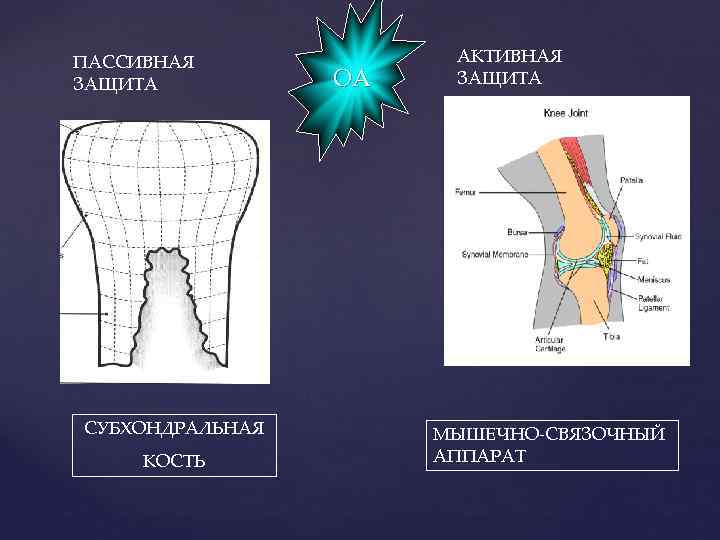

III. Разрушение хряща при остеоартрозе: дисбаланс синтеза и разрушения матрикса • Увеличение ММП • ЦОГ 2→ПГЕ 2 • Апоптоз хондроцитов • Деградация протеогликанов • Деградация коллагена ПОВРЕЖДЕНИЕ • Снижение синтеза протеогликана • Снижение синтеза коллагена • Уменьшение содержания воды • Снижение эластичности РЕПАРАЦИЯ

III. Разрушение хряща при остеоартрозе: дисбаланс синтеза и разрушения матрикса • Увеличение ММП • ЦОГ 2→ПГЕ 2 • Апоптоз хондроцитов • Деградация протеогликанов • Деградация коллагена ПОВРЕЖДЕНИЕ • Снижение синтеза протеогликана • Снижение синтеза коллагена • Уменьшение содержания воды • Снижение эластичности РЕПАРАЦИЯ